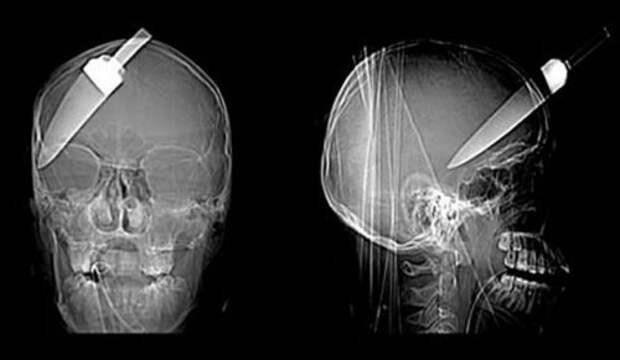

16-летний подросток обманул смерть, когда ему в голову вонзили 12-сантиметровый нож. Подростка отвезли в больницу с кухонным ножом, торчащим из его лба.